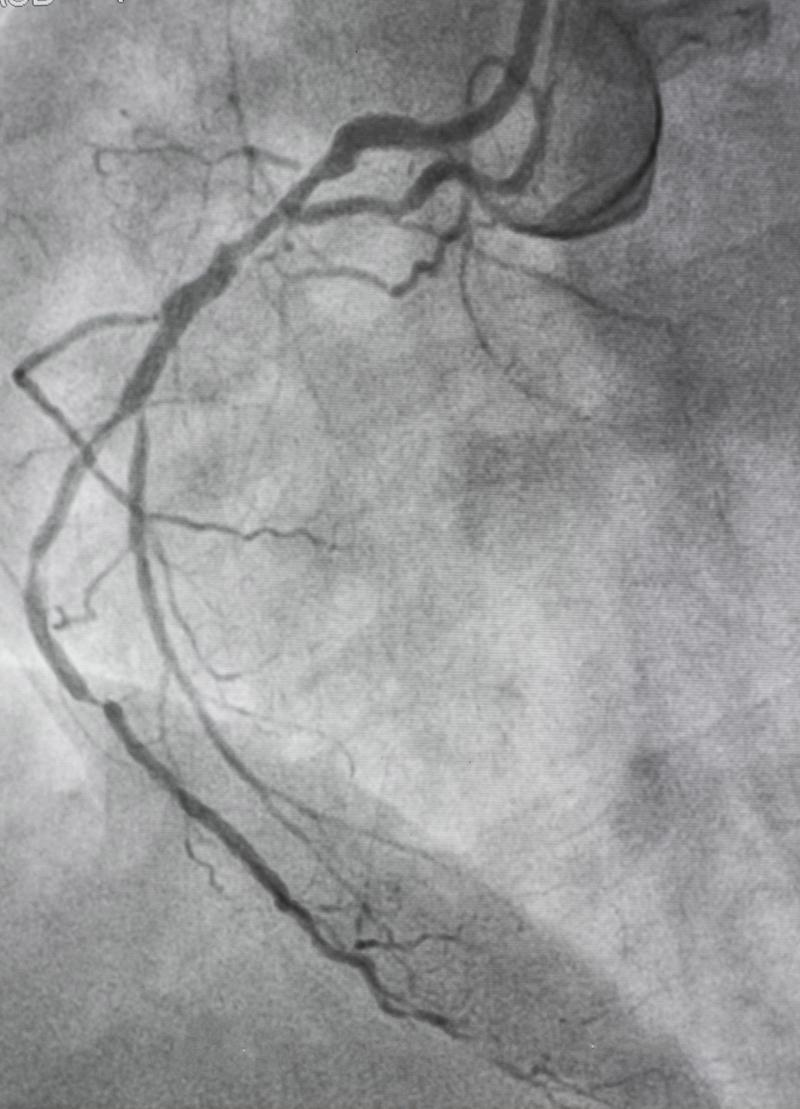

cta与冠脉造影的区别

1、冠脉CTA与冠脉造影的主要区别如下检查方式冠脉CTA通过注入造影剂,在CT扫描下观察冠状动脉的情况,主要依赖于影像学技术冠脉造影是一种更为直接和精确的检查方法,通常需要在导管室进行,通过特定的导管将造影剂直接注入...